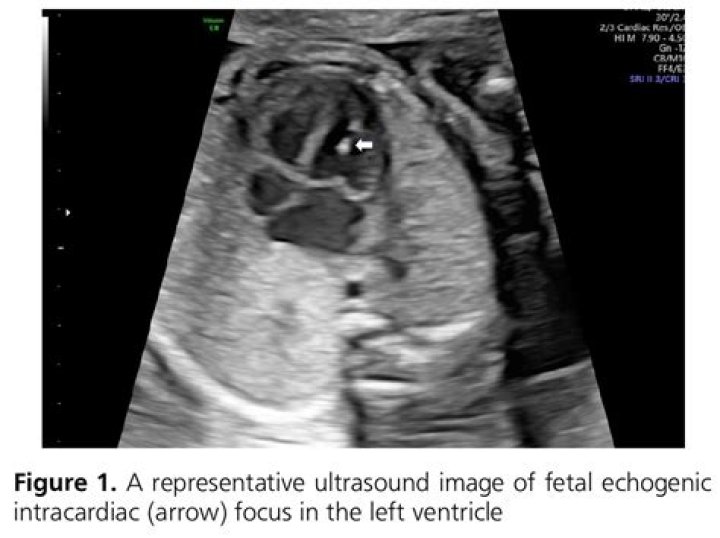

Echogenic foci within the left ventricle of the heart have been found in a minority of fetuses and generally are believed to be a normal variant. Echogenic